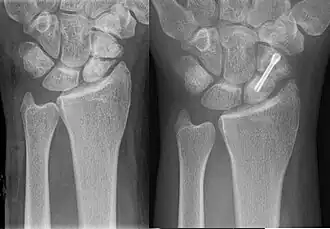

El punto de movimiento puede ser tratado con estimulación eléctrica, lo cual puede desencadenar que las células óseas formen la estructura de hidroxiapatita que evita que el hueso se doble. Más recientemente las pseudoartrosis se tratan con injerto de hueso, fijación interna y externa, incluyendo una técnica originalmente desarrollada por Ilizarov, que se utiliza para comprimir los huesos en el sitio de la fractura.[2] Ilizarov originalmente utilizó rayos de bicicleta, la técnica de marco espacial de Taylor es similar..

Para estabilizar los fragmentos del hueso fracturado se utilizan placas de metal, pernos, tornillos y varillas, que pueden ser atornillados o colocados en el interior del hueso.